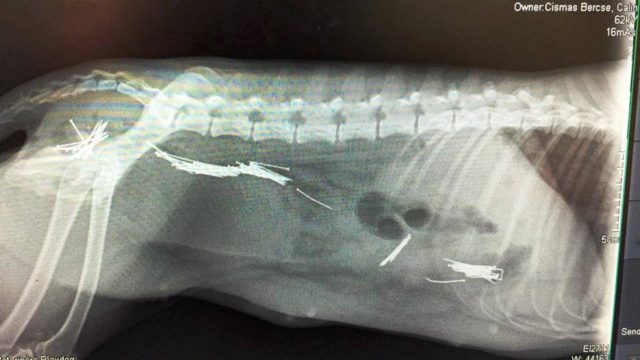

Cruzime fără margini la Arad. O femeie i-a dat cățelei sale gestante să înghită cuie și bolduri, pentru a o omorî.Din fericire, vecinii femeii au văzut când patrupedul a început să regurgiteze cuiele ingerate și au apelat la o asociație pentru protecția animalelor. Voluntarii au venit, au luat cățelușa, pe care au dus-o direct la veterinar pentru a fi operată pentru a-i fi scoase din sistem obiectele metalice.

„I-am scos o mare parte din ele, dar este necesară o a doua intervenţie chirurgicală” – a spus medicul veterinar Wili Glaser, citat de criticarad.ro.

sursa foto: criticarad.ro